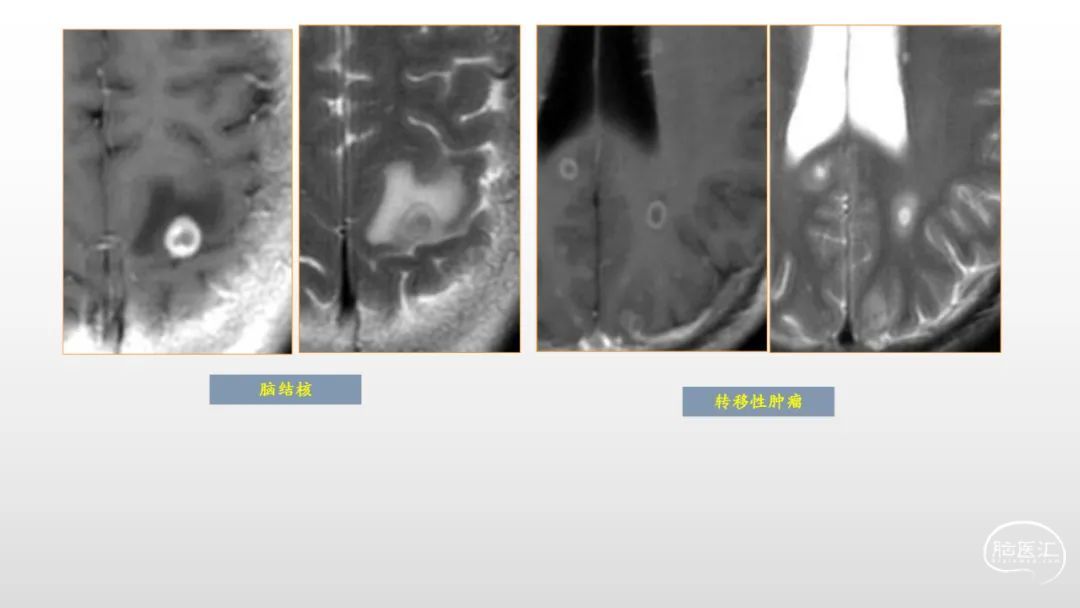

颅脑影像诊断基础知识讲座:感染和免疫性疾病1